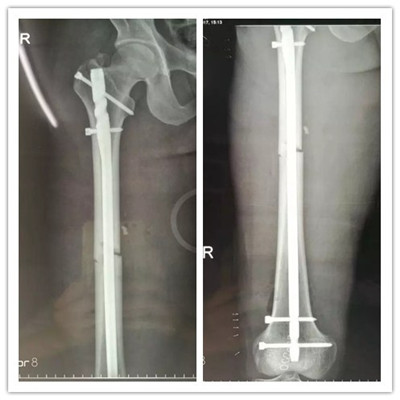

經(jīng)過慎重考慮和周密的術(shù)前計(jì)劃,羅軍主任帶領(lǐng)帶領(lǐng)科室團(tuán)隊(duì)用骨折閉合復(fù)位髓內(nèi)釘固定的微創(chuàng)方法為患者進(jìn)行手術(shù)。 近90分鐘的精心手術(shù),骨折處沒有切開,采用間接復(fù)位的方法就使骨折塊達(dá)到了解剖復(fù)位,并用微創(chuàng)切口導(dǎo)入髓內(nèi)釘對(duì)骨折進(jìn)行了牢固的固定,圍手術(shù)期沒有輸血,醫(yī)療費(fèi)用也明顯降低。

▲骨折的完美復(fù)位和內(nèi)固定

由于傷口小,出血少,術(shù)后疼痛很快減輕,患者術(shù)后僅一天就可以開始扶拐下地活動(dòng)并進(jìn)行康復(fù)鍛煉。